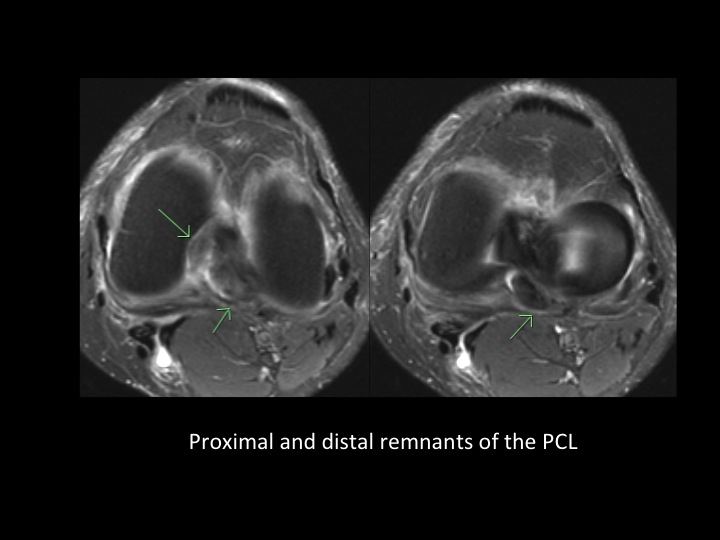

70F continued pain 4 months after fall

PCL tears rarely have a focal fluid signal defect, but typically appear thickened and frayed with increased intrasubstance signal. Despite the presence of a fluid defect in this case, I almost missed it. Ive noticed that the meniscofemoral ligaments fall into the defect, and that is what made me realize the PCL is torn. Anyone have cases they want to share? I think its a good sign. Oh, and theres a peripherally displaced meniscal flap tear with subtle remodeling of the tibial cortex. Reference article.

posterior cruciate ligament ( RID2784 )